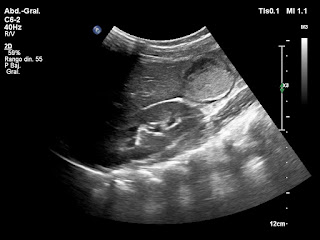

Paciente de 12 años con dolor abdominal. Remitida para estudio de masa intraabdominal.